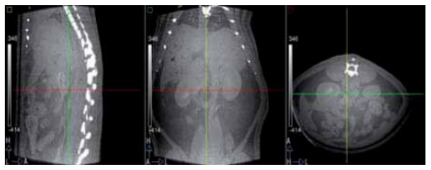

Small animal studies of different modalities require certain image processing tools to be properly visualized and analyzed. We present a multimodality workstation that performs these tasks for different image modalities: positron emission tomography (PET) and computed tomography (CT). Different import formats are accepted (RAW, Interfile, Analyze, DICOM) and also exported. The animal studies can be displayed in different ways, providing always a tri-planar viewer that shows transaxial, coronal and sagital views synchronized. Several basic tools are always available, like window/level and color table setting, image reformatting (affine transformation), distance and angle measures or line profiles. Analysis module allows segmenting three dimensional Regions of Interest (3-D ROIs) using not only manual but also semi-automatic methods like thresholding and region growing.